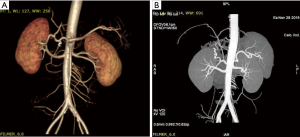

After routine en bloc acquisition of the donor liver, pancreas, and both kidneys, the abdominal aorta was cut between the renal artery and the SMA, the inferior vena cava was transected below the liver and above the right renal vein, the donor pancreas and liver were preserved, and the renal junction kidney group was trimmed. The surrounding tissues, including lymphatic vessels, the hepatic plexus, and surrounding connective tissue, were carefully dissected at the hepatic pedicle at the first porta hepatis. The common bile duct, hepatic portal vein, and PHA were freed from the right to the left, respectively. The distal part of the common bile duct was transected and doubly ligated with no. 7 and 4 silk sutures, the hepatic portal vein was transected approximately 1.5–2 cm away from the outlet of the pancreas, and the PHA was freed in the direction of the pancreas. The common hepatic artery and gastroduodenal arterial arch could be observed, the arterial variation was explored, then the integrity of the arterial arch was obtained. The PHA was transected approximately 0.5 cm away from the distal end of the arterial arch, the PHA transection was closed with a 5-0 atraumatic vascular suture, and the opening of the donor liver end was examined (Figure 1). If the hepatic artery was variant, the variant hepatic artery branches were divided separately (Figures 2 and 3). The SMA and its branches were obtained for liver reserve (Figure 4).

The donor liver was trimmed in vitro and revascularization was performed. After trimming the SMA and its branches and selecting the appropriate branches, the hepatic artery and SMA branches were end-to-end sutured with appropriate atraumatic vascular sutures, fixed at 4 points, then intermittently sutured. The reconstructed artery was then anastomosed end-to-end with the hepatic artery in vivo (Figures 5 and 6). If the PHA of the donor liver was not variable but short, end-to-end anastomosis was performed with the SMA and the PHA of the donor liver in vitro, and end-to-end anastomosis was performed between the SMA of the donor and the PHA of the recipient liver after the portal vein was opened (Figure 7).

Of the 17 recipients, 14 were male and 3 were female, aged between 27 to 56 years. The MELD scores ranged from 1 to 35, and the Child-Pugh classifications were A to C. A total of 15 cases were modified piggyback liver transplantations, and 2 cases were classical piggyback liver transplantations. The intra-operative hemorrhagic volume was 300–6,000 mL, blood transfusion volume was 800–10,955 mL, warm ischemia time was 0 min, cold ischemia time was 5–8 hours, and the anhepatic period was 32–57 min, with an average of 44.5 min. The hospital stays ranged between 34–120 days, with an average of 61.3 days, and the ICU stays ranged between 1–8 days, with an average of 2.83 days. The patients were followed up for 1–96 months, and the prognosis was good. The color Doppler ultrasound of the transplanted liver showed that there were no obvious abnormalities of the blood flow signal of the hepatic artery. The computed tomography angiography (CTA) of the transplanted liver showed that the direction of the transplanted hepatic artery was normal, and the blood flow filling was normal (Figure 8). Postoperative bilirubin and transaminase levels decreased steadily (Figures 9-11). One patient developed hepatic artery stenosis (HAS) 3 months after surgery, and the stenotic segment disappeared after stent placement, whilst all other patients had no vascular complications. All patients had no biliary complications, and no acute/chronic rejection occurred.